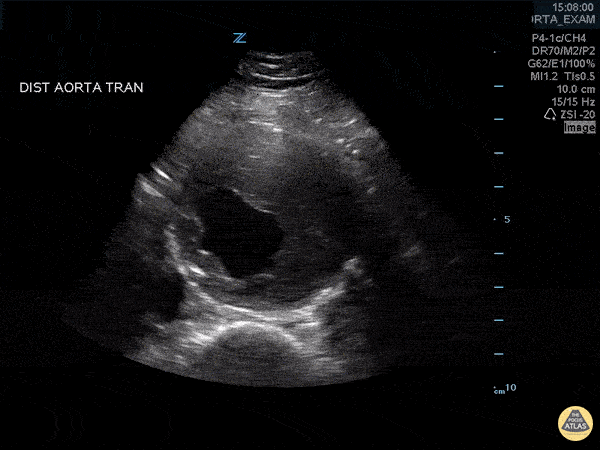

Aorta - Abdominal Aortic Aneurysm with Thrombus

Approximately 6 cm abdominal aortic aneurysm with intramural thrombus. Frances Russell, MD, RDMS Assistant Professor of Emergency Medicine Division Chief, Ultrasound Fellowship Director, Ultrasound